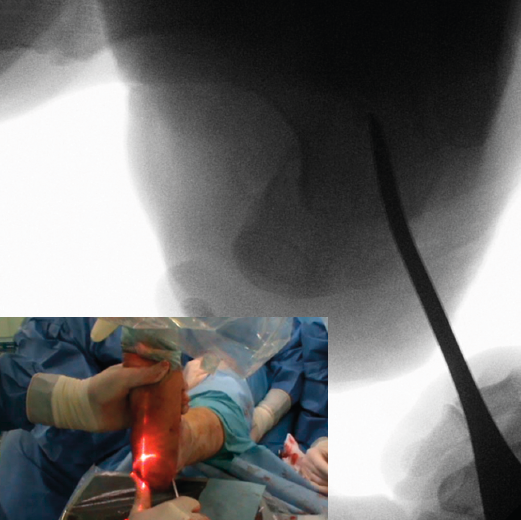

Corrección

Una vez completada, se desplaza la tuberosidad del calcáneo manualmente en la dirección necesaria para la corrección de la deformidad y se introduce un periostotomo a través de la incisión en el escalón que queda tras el desplazamiento para aumentar y mantener dicho desplazamiento. En caso de pie plano valgo, el desplazamiento es medial y se introduce el periostotomo en dirección anterior en la esponjosa del cuerpo del calcáneo para aumentar la traslación (Figuras 7 y 8). En caso de pie cavo varo, el desplazamiento es lateral y se introduce el periostotomo en la esponjosa de la tuberosidad.

Figura 7. Imagen fluoroscópica de la traslación de la tuberosidad con un periostotomo (imagen anteroposterior) y su correspondencia en cirugía.

Se debe mantener la rodilla flexionada para evitar que la tensión del Aquiles nos limite el desplazamiento.

Figura 8. Imagen fluoroscópica de la traslación de la tuberosidad con un periostotomo (imagen axial) y su correspondencia en cirugía.